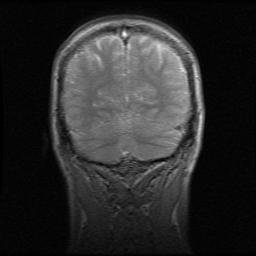

Frontal plane brain.